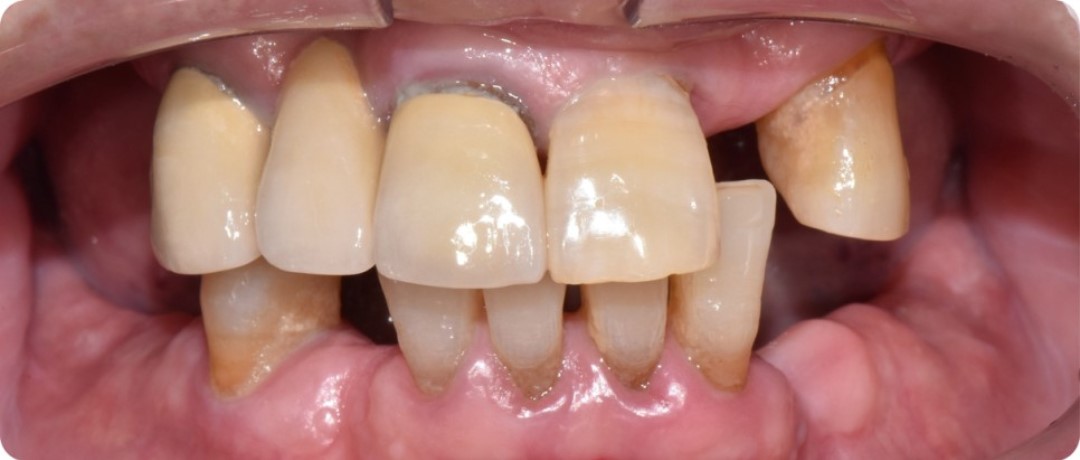

2023년 7월 내원 당시 구강 상태

어떤 치료를 받으셨는지?

앞서 말씀드렸던 것처럼, 김태수님은 잇몸뼈가 원래 많이 부실하셨던 데다가

저작력도 강한 편이어서 임플란트 직경이 두꺼운 걸로

위, 아래 각각 10개씩 임플란트를 심어 드렸는데요.

구강 사진을 봐도 보철물이 상당히 자연스럽고

교합 또한 안정적으로 잘 설계된 모습입니다.